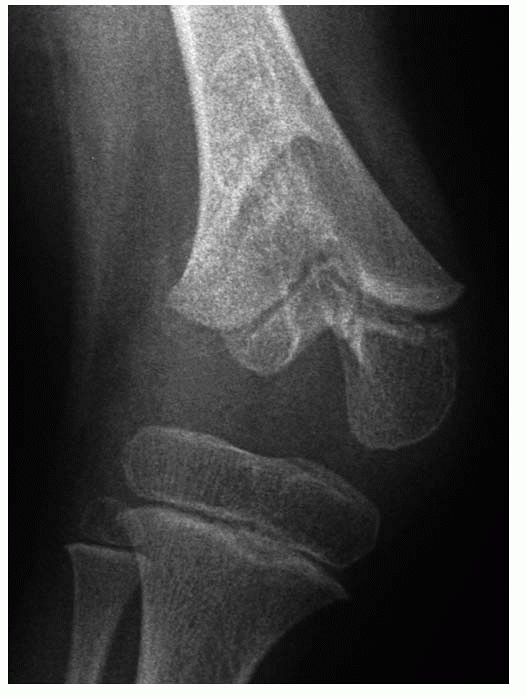

distal humerus, high-energy injuries produce either a T-condylar or

other complex pattern of injury, with at least three fragments,

resulting in a combination of physeal and epiphyseal injuries (Fig. 5-21).

These fractures are important because they disrupt the articular

surface, violate all the physeal layers in crossing from the epiphysis

to the metaphysis, and, with displacement, may result in

metaphyseal-epiphyseal cross-union (see Fig. 5-22B).39,58

The latter occurrence almost invariably results in subsequent growth

disturbance. This fracture pattern is frequent around the medial

malleolus, but may occur in other epiphyses. Lateral condylar fractures

of the distal humerus and intra-articular two-part triplane fractures

of the distal tibia may be thought of as complex Salter-Harris type IV

fractures. Rang120 described an

extra-articular variant (as if a peripheral extra-articular

epiphyseal-physeal-metaphyseal fragment were “scooped out” from the

rest of the bone) sometimes referred to as a Salter-Harris type VI

fracture pattern.

| Figure 5-20 A. Salter-Harris type III fracture of the distal femur. B. Fixation with cannulated screws. |